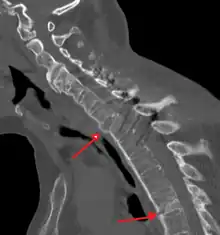

The earliest changes demonstrable by plain x–ray shows erosions and sclerosis in sacroiliac joints. Progression of the erosions leads to widening of the joint space and bony sclerosis. X-ray spine can reveal squaring of vertebrae with bony spur formation called syndesmophyte. This causes the bamboo spine appearance. A drawback of X-ray diagnosis is the signs and symptoms of AS have usually been established as long as 7–10 years prior to X-ray-evident changes occurring on a plain film X-ray, which means a delay of as long as 10 years before adequate therapies can be introduced.[21]

Lateral X-ray of the mid back in ankylosing spondylitis -

CT scan showing bamboo spine in ankylosing spondylitis -